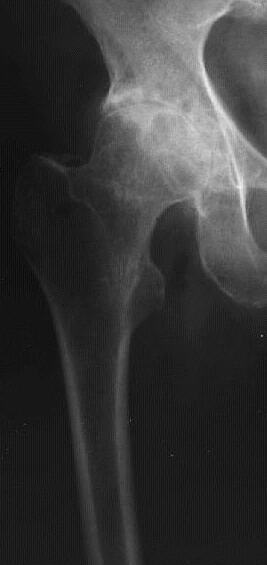

Vergleichen Sie die linke (physiologische) Aufnahme mit der rechten (pathologischen) Aufnahme